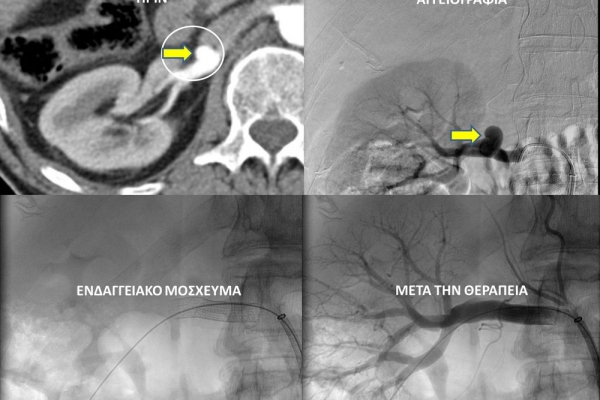

Ο επεμβατικός ακτινολόγος θα προσεγγίσει το παθολογικό αγγείο ενδοαυλικά και με απεικονιστική καθοδήγηση θα τοποθετήσει τακατάλληλα υλικά αποκατάστασης του ανευρύσματος. Υπάρχουν μια σειρά από επιλογές θεραπείας και η θεραπεία, που θα επιλεχθεί, εξαρτάται από την τοποθεσία και το σχήμα του ανευρύσματος.Μία πιθανή επιλογή για ενδαγγειακή θεραπεία περιφερικής αρτηρίας είναι η χρήση ενδαγγειακού μοσχεύματος stent-graft. Εναλλακτικά, το εσωτερικό του ανευρύσματος μπορεί να γεμίσει με εμβολικό υλικό (μικρά σπειράματα-coils ή ειδικη κόλλα), το οποίο εμποδίζει την ροή αίματος στο ανεύρυσμα.